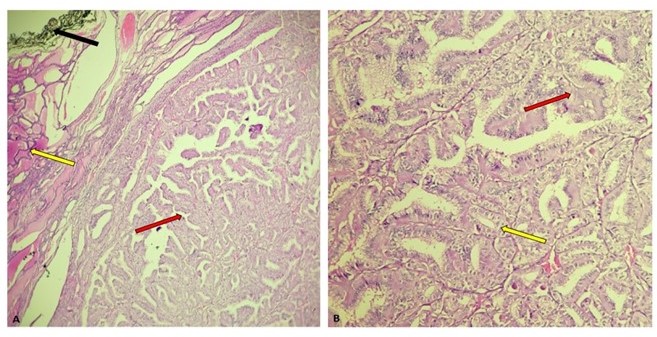

El examen histológico de la lesión nodular del lóbulo izquierdo reveló una neoplasia maligna de linaje epitelial constituida por células cúbicas con núcleos que exhibían aumento del tamaño, superposición, aclaramiento de la cromatina, contornos nucleares irregulares y pseudoinclusiones. Las células se organizaban en papilas y folículos. El tumor distó 0,1 cm del margen de resección y no presentó angioinvasión, tampoco invasión linfática ni perineural. El lóbulo derecho e istmo fueron histológicamente benignos. Con base en lo anterior, se realiza el diagnóstico de MPT (Figura 2 y 3).

Microscópicamente el MPT puede tener múltiples patrones arquitectónicos asociado a las características nucleares típicas del CPT. Usualmente tienen una configuración estrellada o en forma de cicatriz, puede ser encapsulado o no encapsulado y puede tener un borde esclerótico. El patrón de crecimiento es papilar, folicular o una mezcla de ambos. Las células son cúbicas y los núcleos tienen superposición, contornos irregulares, pseudo-inclusiones y aclaramiento de la cromatina. En menor proporción se pueden observar otros patrones como el de células altas (3).